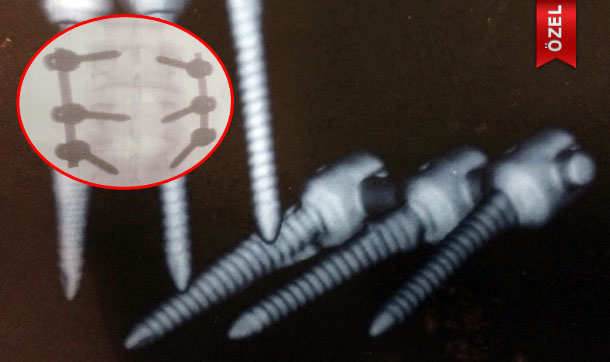

İstanbul'daki bir özel hastanede bel fıtığı ile disk kayması sorunu yaşayan Hüsnü Kilitçioğlu isimli vatandaşın omurgasına ameliyatla vida takıldı. Ağrılarının artması üzerine hastaneye giden hastanın omurgasına takılan vidalardan birisinin kırıldığı belirlendi. Hastanın şikayetçi olması üzerine ameliyatı yapan Doç. Dr. M.S.'ye "taksirle bir kişinin yaralanmasına sebebiyet vermek" suçundan 2 yıla kadar hapis istemiyle dava açıldı.

İstanbul Asliye Ceza Mahkemesi'nde açılan davanın iddianamesine göre ağır işlerde çalışan ve belinde disk kayması ile bel fıtığı rahatsızlığı oluşan Hüsnü Kilitçioğlu, 24 Ocak 2012 tarihinde Şişli'de özel bir hastanede Doç. Dr. M.S tarafından ameliyat edildi. Ancak ameliyattan sonra ağrılarının daha da arttığını fark eden Kilitçioğlu'nun bel tomografisi çekildiğinde, ameliyat sırasında omurgasına takılan vidalardan birisinin kırıldığı ortaya çıktı. Kilitçioğlu'nun avukatı Nafiz Aydın da müvekkilinin uygulanan hatalı tedavi ve orijinal olmayan imitasyon vida takılması nedeniyle sakat kaldığını belirterek operasyonu yapan doktordan şikayetçi oldu. Soruşturma kapsamında mağdur olduğunu iddia eden Kilitçioğlu'na ait tüm tomografi ve rapor sonuçları incelenmek üzere Adli Tıp Kurumu'na gönderilerek rapor talep edildi.

Hazırlanan 25 Ağustos 2014 tarihli Adli Tıp Kurumu raporunda, omurgaya takılan vidalardan birisinin kırık olduğunun tespit edildiği, ancak bel fıtığı ameliyatı sonrası ortaya çıkan bu durumda her türlü özene rağmen ameliyatı yapan doktora bir kusur atfedilemeyeceği, ameliyatın her şeye uygun olarak yapıldığı yönünde görüş bildirdi. Hazırlanan bu rapor üzerine Doç. Dr. M.S hakkında kovuşturmaya yer olmadığına dair "takipsizlik" kararı verildi.

İstanbul Asliye Ceza Mahkemesi'nde görülen davanın ilk duruşmasında sanık sıfatıyla hakim karşısına çıkan M.S, ifadesinde "" Tüm malzemeler "CE" belgelidir (Ürünün Avrupa ürün mevzuatlarına uygunluğunu gösteren kısaltma) ve lisanslıdır. Vidalardan birinde kırık meydana gelse de ameliyatın olası komplikasyonlarındandır. Kullanılan malzeme yerli de olsa "CE" belgeli olup hastanede kullanılan malzemelerdendir. Bu hastada kullanılan malzeme de İzmir'de üretim yapan bir firmaya aittir. Bu vidalardan kaç tane hastaya kullandığımı bilemem, ama kayıtlarda vardır. Suçlama vidanın kırıldığı yönündedir. Benim doktorluk mesleğime yönelik bir suçlama değildir. Ben her ameliyatta her omurgaya bir tane vida takarım. Eğer her bir omurgada birden fazla vida varsa bu ikinci operasyon anlamına gelir. Ben de ikinci operasyonu yapmadım." dedi.

Müşteki avukatı Nafiz Aydın, ise mahkemeye sunduğu dilekçede, "Müvekkilim bu hastanenin sağlık hizmetleri bünyesinde ağır işte çalıştırılmış ve belinden sakat kalmıştır. Doktordan başka şikayetçi olduğumuz hastanenin müdürü, medical firma yetkilileri ve hastanenin sağlık hizmetleri şirketine de takipsizlik kararı verilmiştir. Bu takipsizlik kararına da itiraz ettik. Müvekkilim felç olma tehlikesiyle karşı karşıya kalmıştır. Ucuz vida kullanarak müvekkilimin vücudunda vidanın kırılmasına neden olmuştur. Kırılan vidayı çıkarmak yerine üstüne ikinci vida çakarak alttaki vidanın parçalanmasına ve müvekkilimin hareket kabiliyetinin sıfırlanmasına neden olmuştur. İmitasyon vida kullanıldığı için ikinci bir vida daha kırılırsa müvekkilim felç olma tehlikesiyle karşılaşacaktır" ifadelerini kullandı.